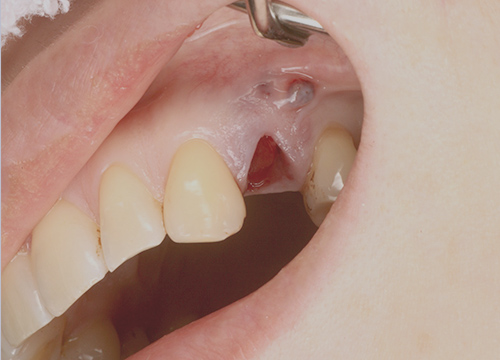

従来のインプラントでは悪くなった歯を抜歯し、骨や歯茎が回復した状態でインプラント手術をおこないます。

歯がなくなると骨は溶け、歯茎は凹んでしまい、前歯などの見た目に大きく関わる部位では、見た目をよくするためだけに、さらに歯茎を切って移植する大掛かりな手術をする必要があり、大きな痛みを伴ったり、治療期間が半年以上大幅にかかってしまう場合があります。

当院ではルートメンブレンテクニックを用いることで、骨や歯茎の減りを最小限におさえることができます。結果痛みも少なく、治療期間も3ヶ月程度となります。

抜歯後

治療後